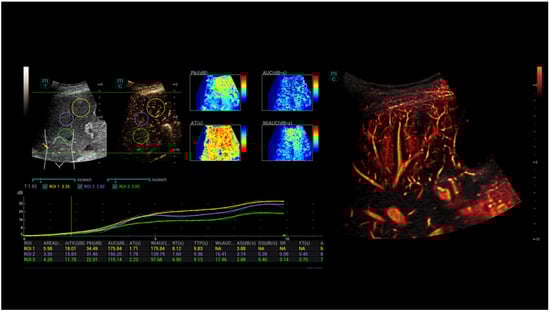

High-Resolution Contrast-Enhanced Ultrasound with SRCEUS for Assessing the Intrahepatic Microvasculature and Shunts in Patients with Hereditary Haemorrhagic Teleangiectasia (Osler’s Disease)

3. Results